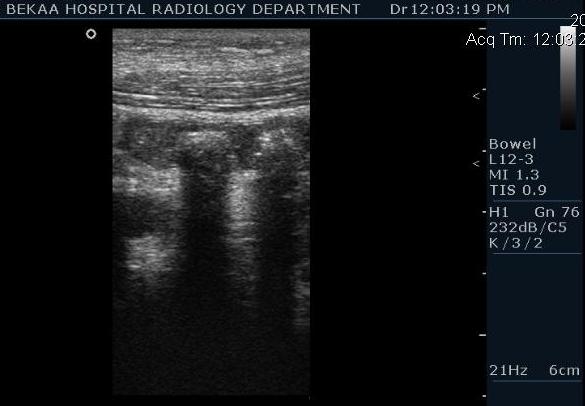

Диагностика острого аппендицита по УЗИ: очень актуальная тема; УЗ аппараты практически есть во всех клиниках; метод доступный и не сложный; главное владеть правильной техникой. Не буду загружать лишней теорией и разными ссылками; поделюсь практическим опытом. У меня линейный датчик 3-12 мегагерц с плавающей частотой; аппарат Филипс HD 11, всегда включаю соно-КТ (9800 цифровых каналов) и гармонику когда смотрю кишечник. Нормальный аппендикс видеть можно; но вопрос зачем??? Как правило, если при наличии достаточного опыта аппендикс не виден; значит скорей всего аппендицита нет. Когда "идешь" на аппендицит то главное по началу набраться терпения и......хорошая компрессия! По началу надо минут 10-15; потом когда появится достаточный опыт; за 2-5 минут можно справится и получить отличную визуализацию. Мочевой пузырь лучше опорожнить; часто он приподнимают тонкий кишечник и может закрыть "окно" через которое будет видно апендикс. Сначала находим слепую кишку потом находим илео-цекальное соединение;

после начинаем производить хорошую компрессию датчиком попрося пациента сообщить в какой точке боль наиболее выражена; медленными движениями датчика сканируем область наибольших болевых ощущений и как правило находим утолщенный отросток. Лучше начинать с поперечной визуализации и идти к верхушке аппендикса что бы убедится что это аппендикс и он заканчивается, а не тонкая кишка (которая если и закончится то только переходя в слепую); потом надо аккуратно развернуть продольно датчик и посмотреть от верхушки аппендикса к слепой. Норма диаметра: 3-4 мм; 5-6 мм под вопросом (клиника решает; но я в катаральный аппендицит не верю); 7-8 мм и больше, не компремируемый (фиксированный отросток)-острый аппендицит! Помимо наличие утолщенного аппендикса; признака "бычьего глаза" (bull-eye sign) при поперечном сканировании; надо обращать внимание на присуствие аппендоколитов в просвете; деструкцию стенки и свободной жидкости в зоне интереса.